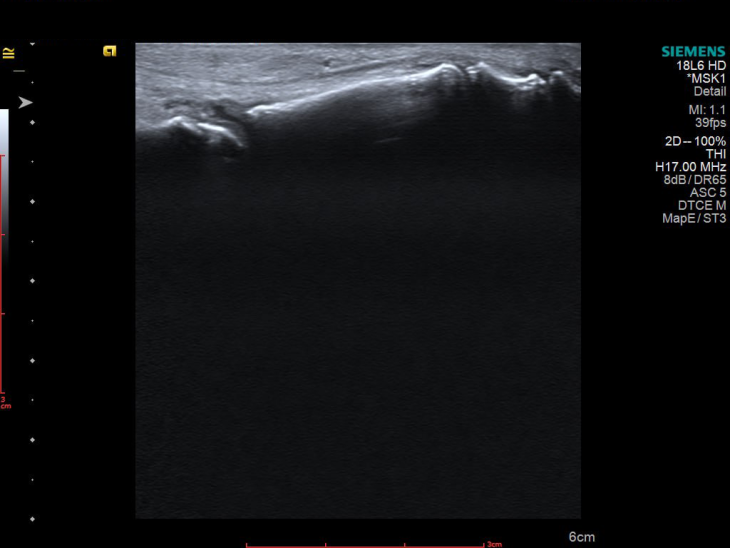

УЗД 3-го пальця продемонструвало не просто запалення, а його розгорнуту, системну картину, а саме виражений випіт у всіх суглобах пальця, потовщені м’які тканини та ознаки ентезиту сухожилків згиначів. Такий комплекс змін вже не вписувався в ізольований подагричний напад.

Картина доповнилася після обстеження гомілковостопного суглоба, бо було виявлено активний теносиновіт.

І що важливо — при всій цій запальній активності УЗД не показало жодної типової для подагри ознаки: ні подвійного контуру, ні тофусів.